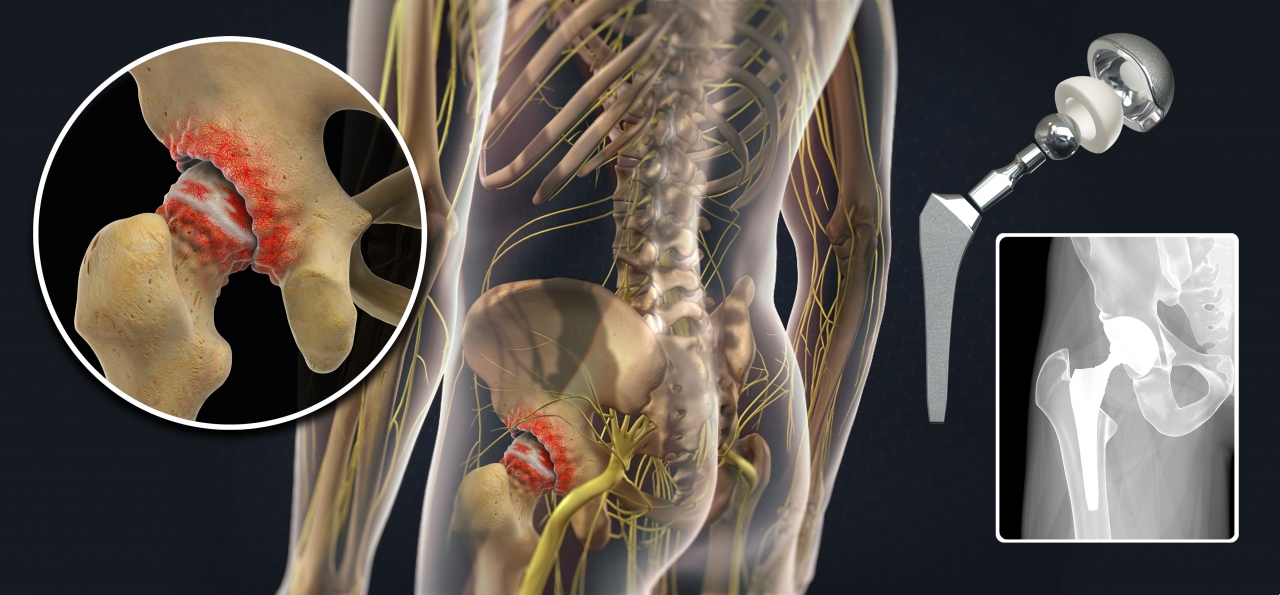

Замена таз сустава

Замена таз сустава 113 фотографий